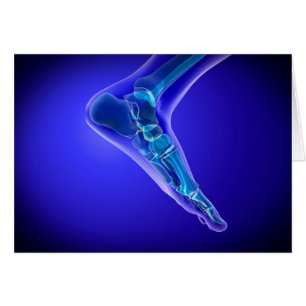

Vue En Rayon X Du Pied Humain 3

Prix de vente 6,48 $CA. Prix Initial 7,20 $CA.